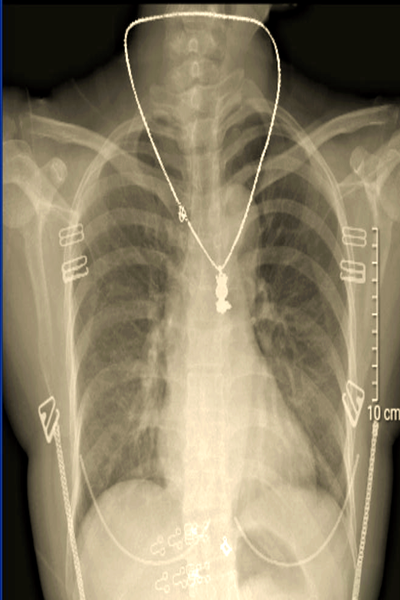

为什么要去除金属首饰?

金属首饰包括项链、手链、戒指等,这些物品由金属制成,可以对放射线产生影响。如果在进行放射科检查时仍戴着金属首饰,它们可能会干扰图像的质量,并干扰医生对患者的准确诊断。因此,在进入放射科之前,患者需要注意将金属首饰摘下来。